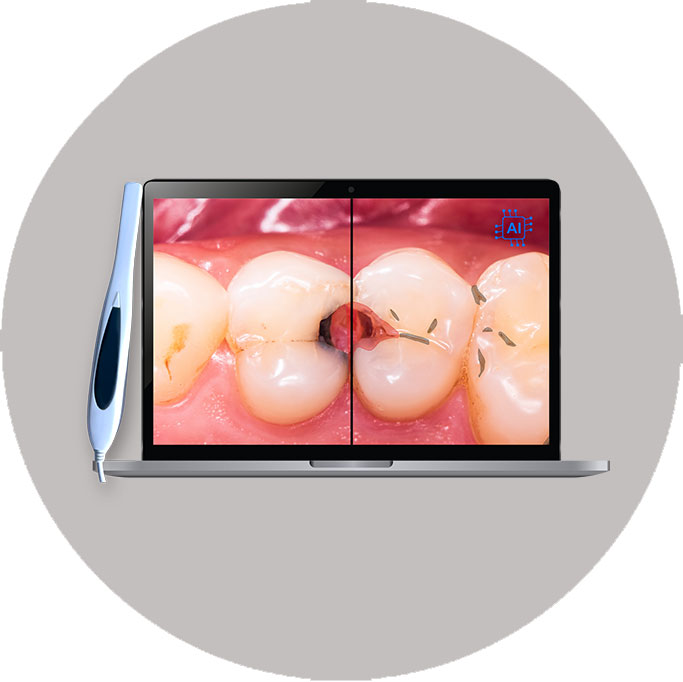

AI Detection via Intraoral Camera

Our AI also works hand-in-hand with an intraoral camera to detect common dental issues, such as cavities or gum problems. You will be able to see your teeth up close on a screen with areas of concern visibly highlighted, making it easier to understand your treatment needs and progress over time.

Benefits:

- Real-time visual check of your teeth and gums

- Encourages preventive care and early treatment

- Makes every visit more interactive and educational